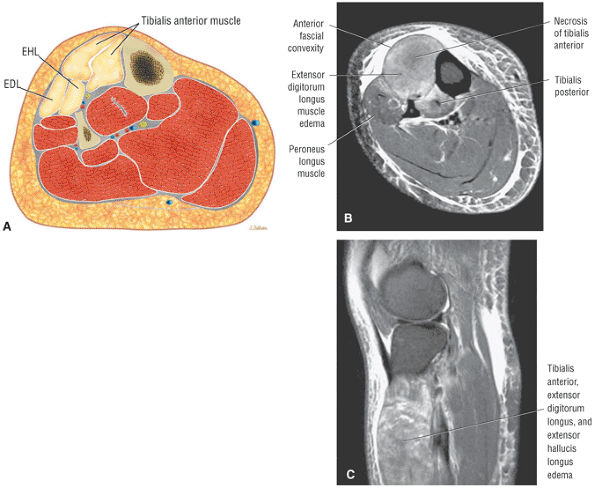

![]() |

|

FIGURE 5.58 ● transverse section through the midcalf shows the anterior and lateral compartments and their contents.